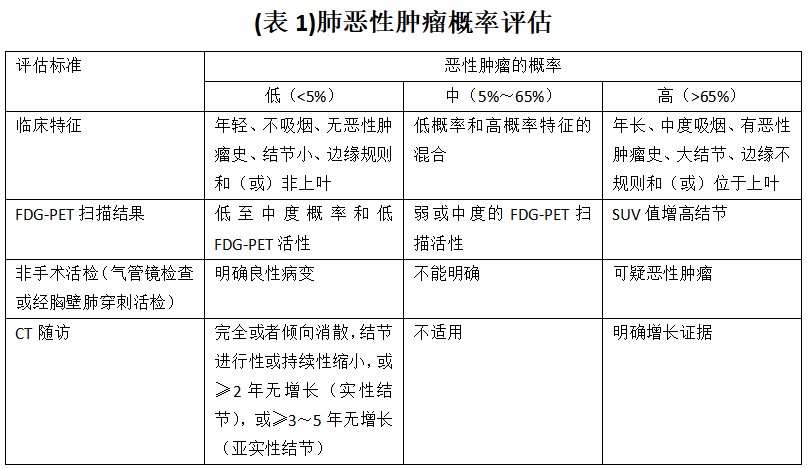

据上述评估手段对肺部结节行肺恶性肿瘤概率评估(见表 1)